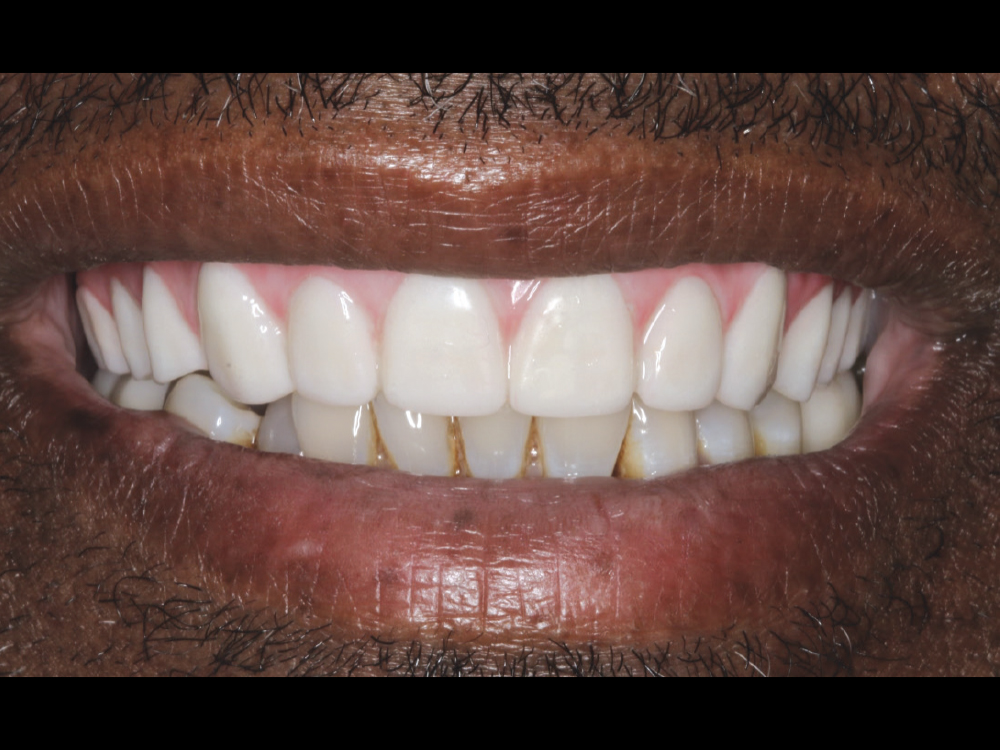

The desire for improved esthetics motivated the patient to seek consultation. A retracted view shows the patient’s anterior misalignment and malocclusion in the maxillary arch. CBCT analysis showed extensive periodontal bone loss that warranted extraction and implant reconstruction in the maxilla and posterior mandible.

Figures 1a, 1b: The desire for improved esthetics motivated the patient to seek consultation. A retracted view shows the patient’s anterior misalignment and malocclusion in the maxillary arch. CBCT analysis showed extensive periodontal bone loss that warranted extraction and implant reconstruction in the maxilla and posterior mandible.